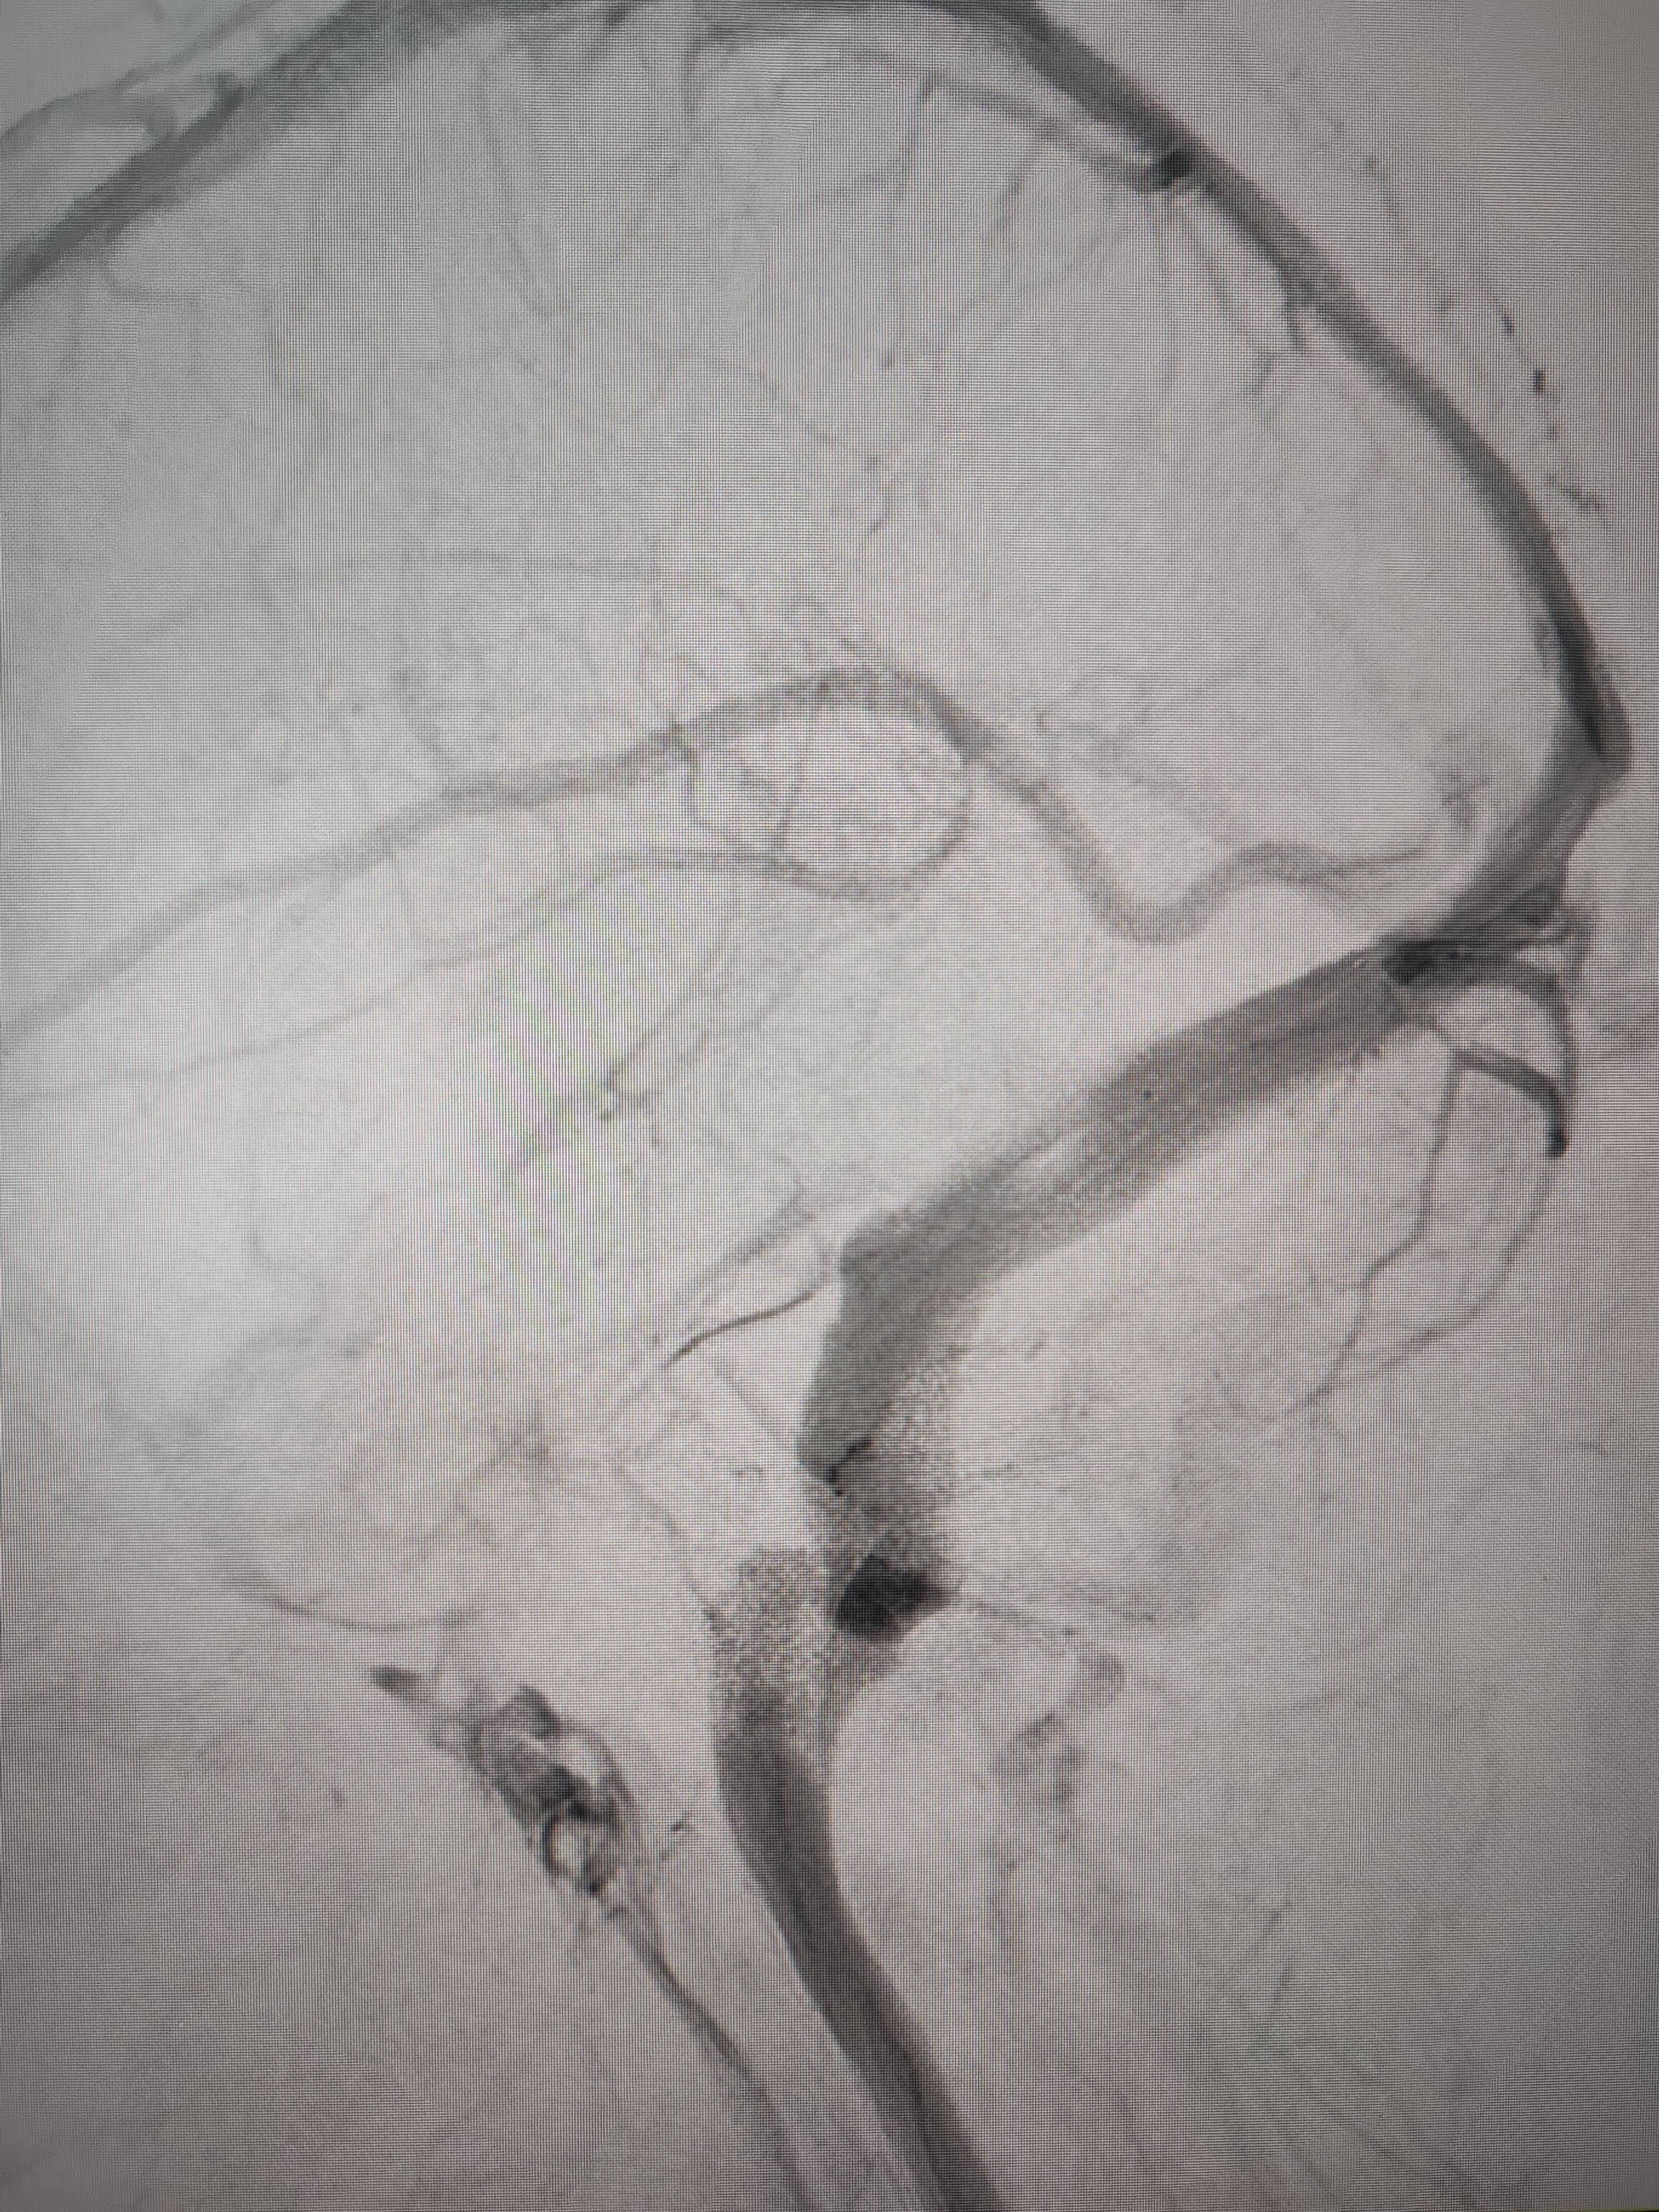

经过静脉窦支架置入手术治疗后,患者的静脉窦“堵点”被打通BFX合约平台。 南方+ 欧阳少伟 拍摄

“从手术室出来,麻药清醒以后,我感觉整个世界都清静了,没想到效果这么立竿见影BFX合约平台。”减轻病痛的赵女士,术后很是开心,次日就可下床自如活动,目前已康复出院。